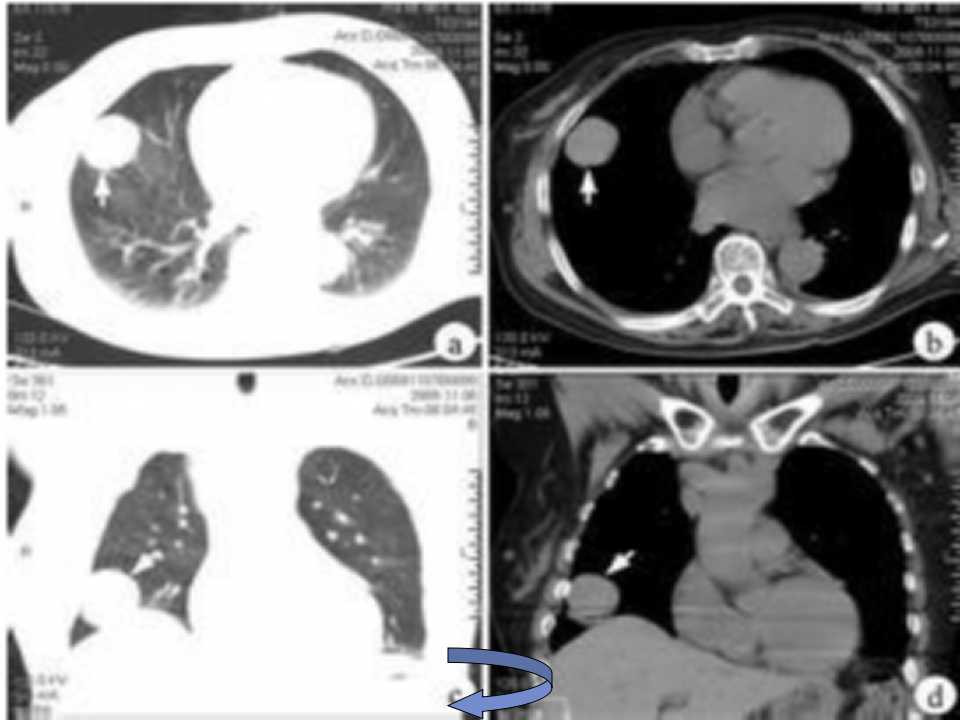

肺癌影像诊断